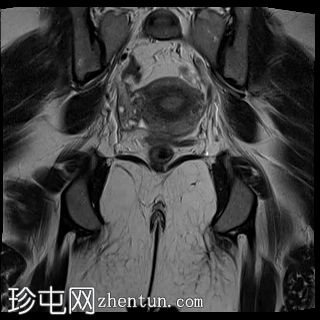

矢状位

T2加权像

MRI特征符合剖宫产术后瘢痕子宫内膜异位症,表现为特征性T1高信号伴T1FS持续存在,T2低信号伴内部高信号灶,病灶边缘浸润于腹前壁肌肉内,以及对比增强。

该病灶累及腹白线并浸润腹直肌,主要位于中线左侧,耻骨联合及结节处腹直肌起点上方。

影像学表现符合病灶内出血成分,提示既往剖宫产瘢痕处存在异位子宫内膜组织。

子宫可见剖宫产瘢痕灶。

未见明确的腹膜内或皮下软组织侵犯。